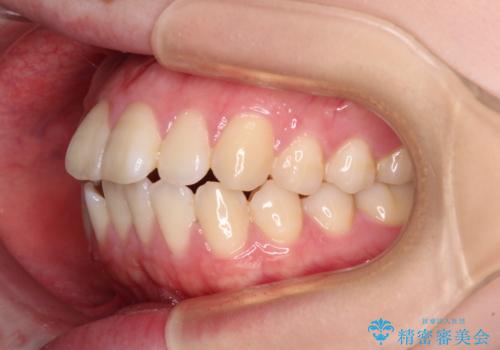

強い舌の突出癖により、上下前歯が前方に飛び出しており、特に上顎前歯は下顎よりも更に前方に位置している状態でした。

上顎前歯をしっかりと後方に移動させるため、口蓋側にアンカースクリューと補助装置を併用し、上下左右の第一小臼歯4本を抜歯し、ワイヤー装置にて矯正治療を行うこととしました。